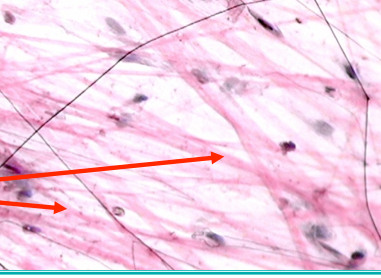

smooth muscle tissue

Involuntary, not striated, spindle-shaped